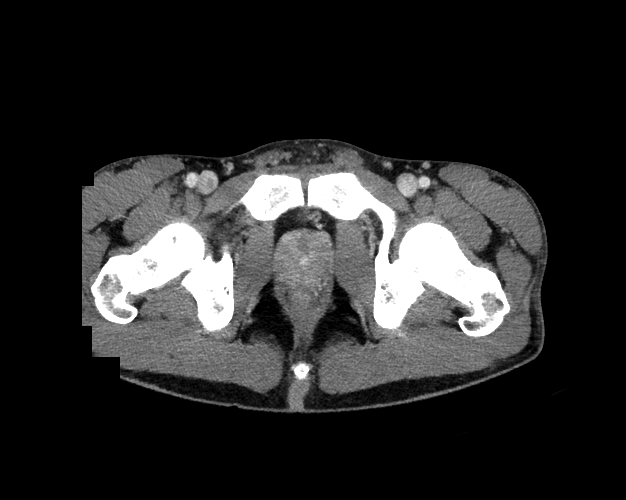

Pelvis

Covers pelvic MRI anatomy.